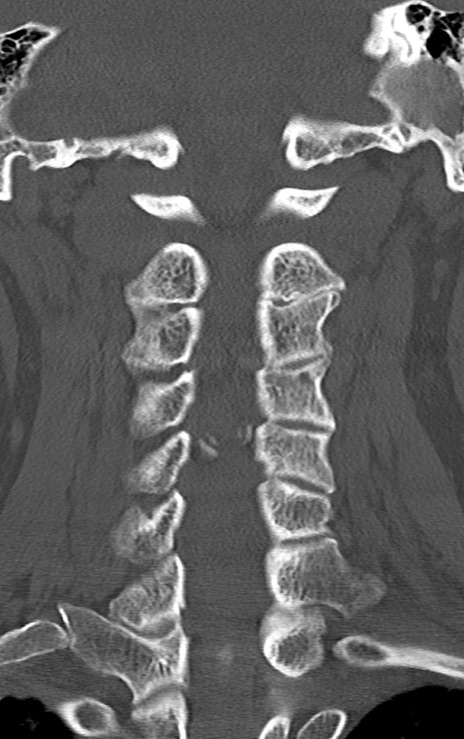

頚椎CT

矢状断像